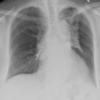

Radiation case 2

Date: 02/10/2005

Views: 3982